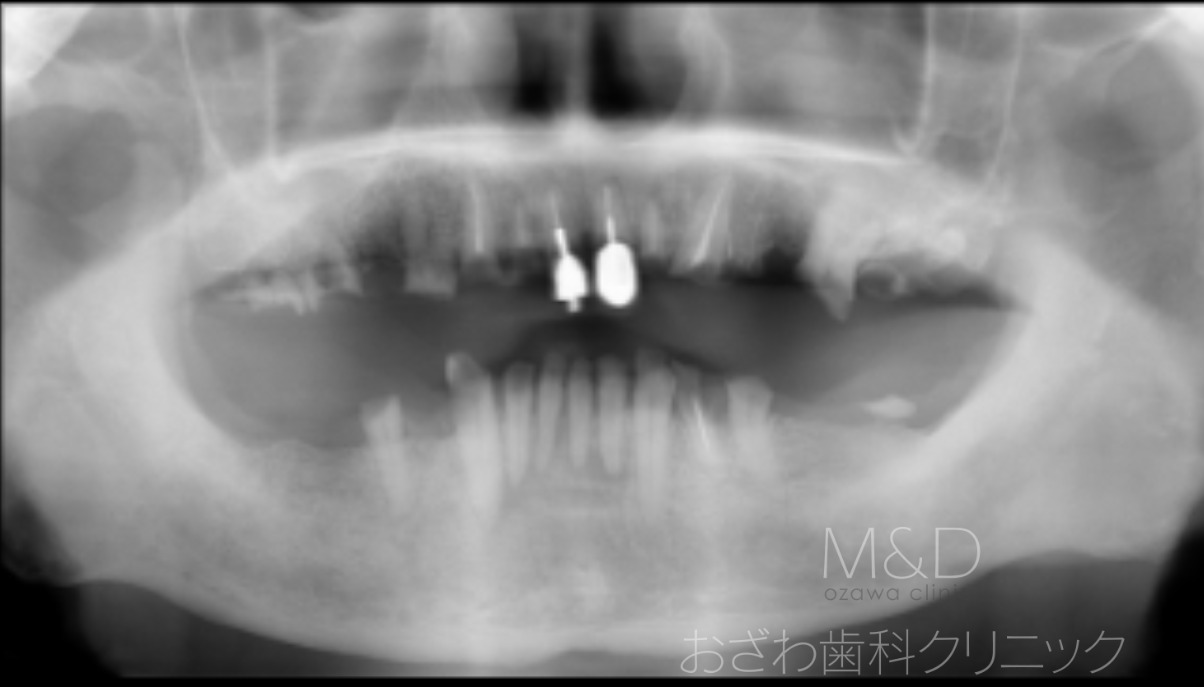

術前

主訴:歯がボロボロで噛めない

上下顎残存歯の抜歯、上顎5本、下顎4本(オールオン4)インプラント